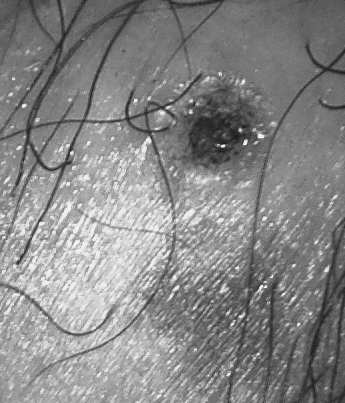

손발 사마귀 제거, 냉동치료 해도 재발한 이유

손발 사마귀 제거, 냉동치료 해도 재발한 이유 손이나 발에 생기는 사마귀 때문에 불편하셨던 분들 많으시...